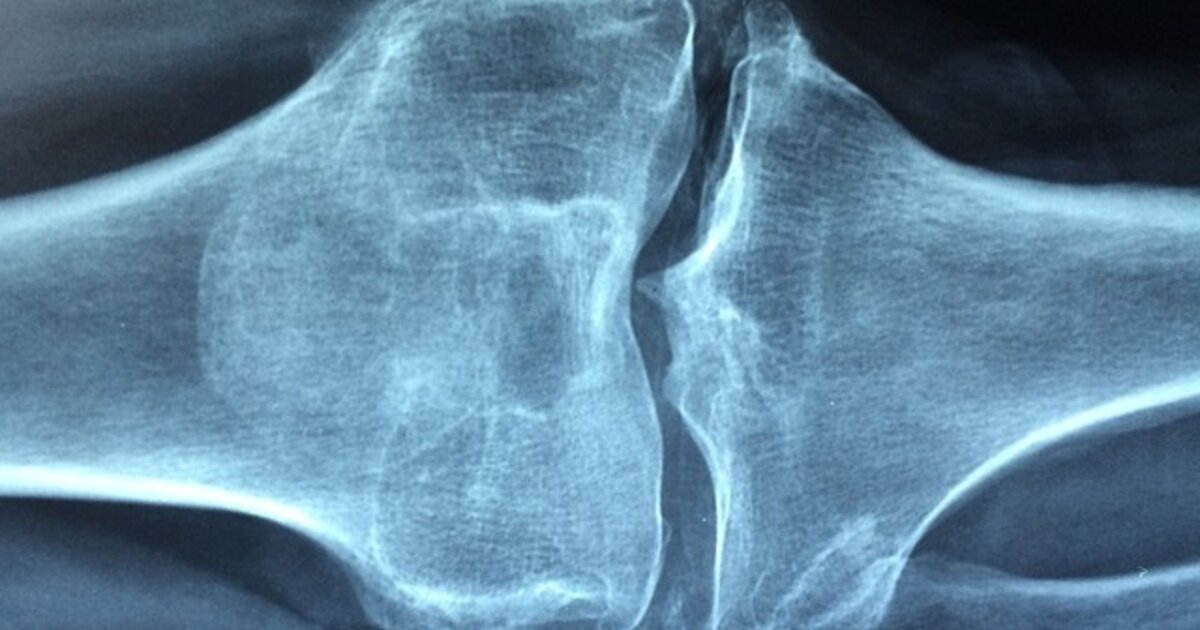

Η οστεοπόρωση είναι μια ασθένεια, που λεπταίνει τόσο πολύ τα οστά, που ακόμη και μια μικρή πτώση ή χτύπημα στην πόρτα του αυτοκινήτου ή σε ένα έπιπλο μπορεί να προκαλέσει κάταγμα. Ένα σπάσιμο μπορεί να συμβεί σε οποιοδήποτε σημείο του σκελετού σας, αλλά τα κατάγματα του καρπού, του ισχίου και της σπονδυλικής στήλης είναι από τα πιο κοινά. Σήμερα, θα δούμε τι πρέπει να κάνεις για να μην πάθεις οστεοπόρωση.

Το να διατηρείτε γερά τα οστά σας είναι ένας έξυπνος στόχος σε οποιαδήποτε ηλικία. Ωστόσο, τα οστά χωρίς κατάγματα γίνονται η μεγαλύτερη προτεραιότητα τις δεκαετίες μετά την ηλικία των 50 ετών, καθώς τα εξασθενημένα οστά οδηγούν σε σπασίματα μία στις δύο γυναίκες και έναν στους πέντε άνδρες.

Μετά την ηλικία των 50 ετών, η απώλεια οστικής μάζας ξεπερνά τον σχηματισμό νέας και η οστική απώλεια επιταχύνεται.